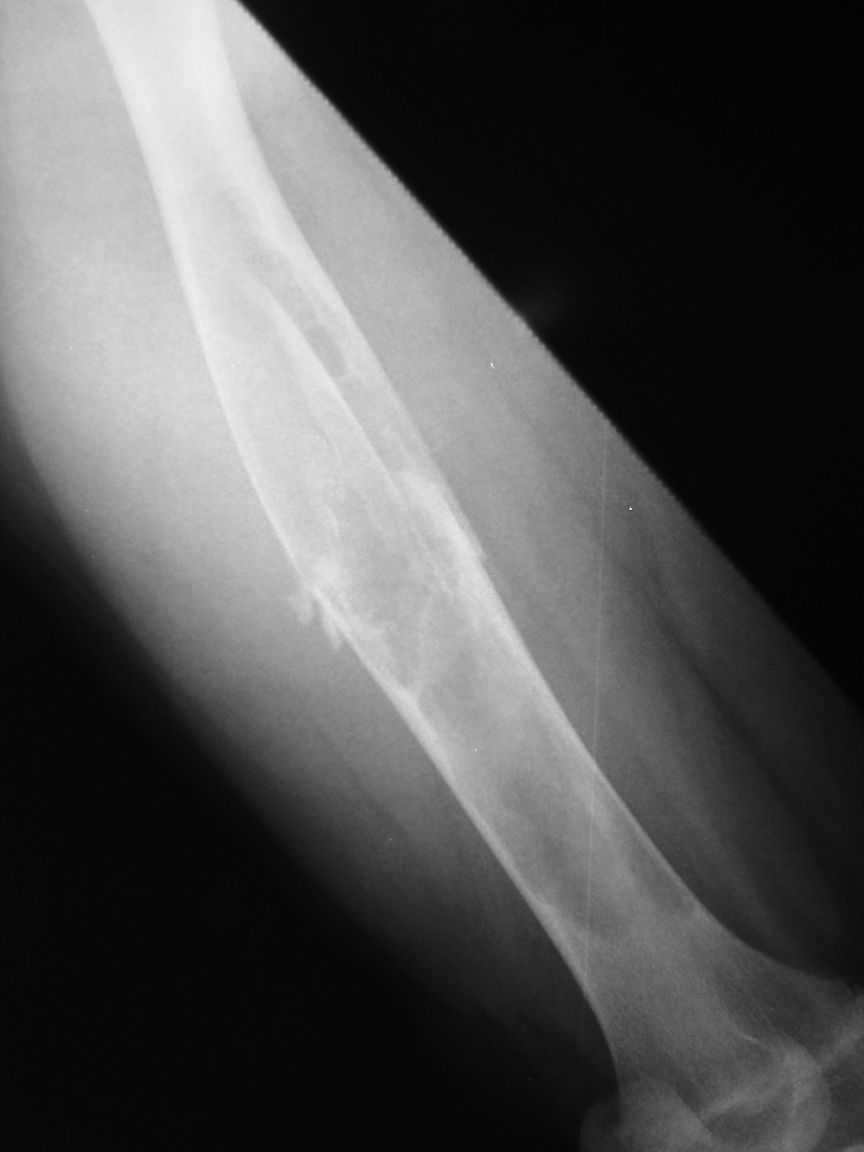

I agree that this case is fibrous dysplasia.

As a method of treetment I propose removal of fibous tissue and cavity allografting, including frozen cortical long graft as an intramedullary nailing. I think it is a good decision without using of any metal construction.